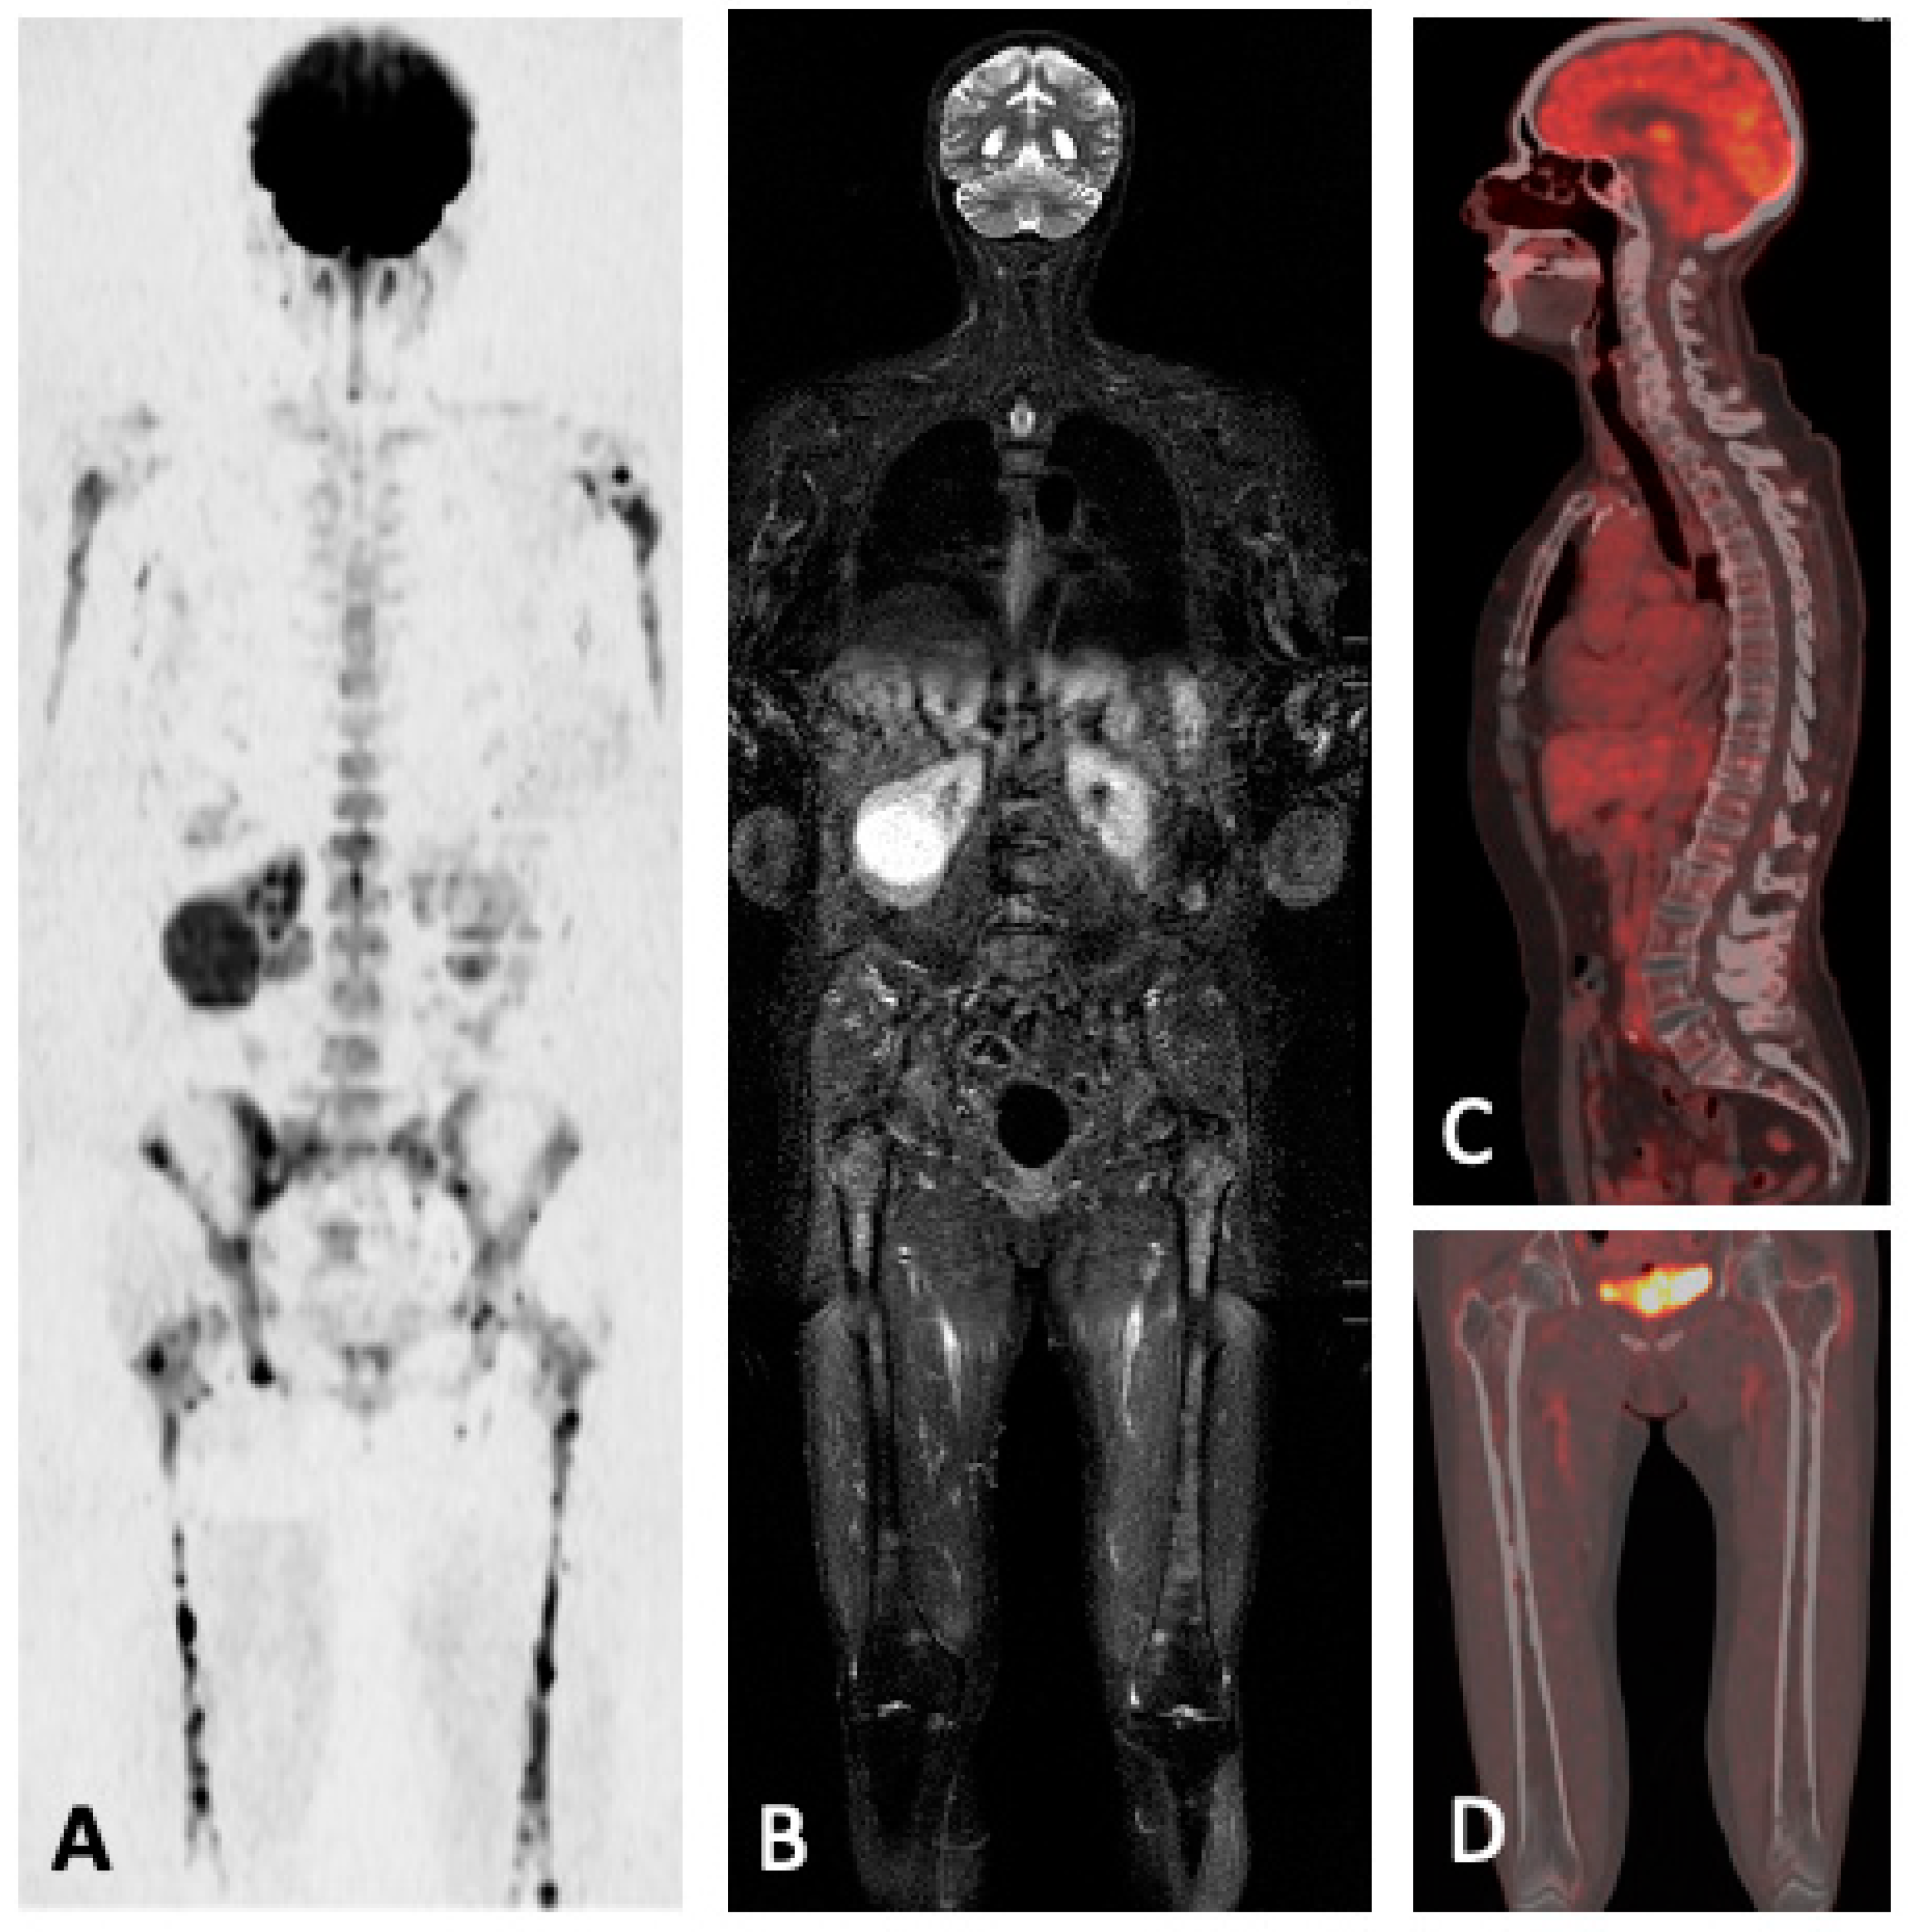

5.1.5. FDG-PET/CT vs. WBMRI

5.2. FDG-PET/MRI